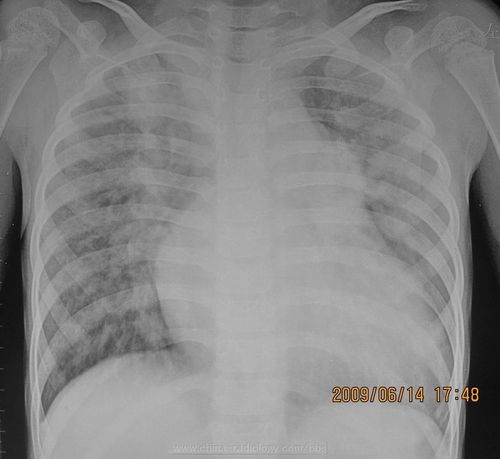

胸透可以看到胸部的軟組織、骨骼(包括胸椎)、縱隔(心臟、大血管、氣管、食管等)、氣管和支氣、胸膜、肺組織等??梢栽\斷肺和氣管的先天性疾病,如發(fā)育異常、肺部的各種炎癥、急慢性支氣管炎、比較明顯的支氣管擴(kuò)張癥、肺氣腫或肺水腫、各型肺結(jié)核、肺腫瘤、胸腔積液、氣胸、縱隔腫瘤、心臟形態(tài)異常等

健康查體最常做的是胸部的X線(xiàn)檢查,最基本的就是胸透。 胸透可以看到胸部的軟組織、骨骼(包括胸椎)、縱隔(心臟、大血管、氣管、食管等)、氣管和支氣、胸膜、肺組織等。

可以診斷肺和氣管的先天性疾病,如發(fā)育異常、肺部的各種炎癥、急慢性支氣管炎、比較明顯的支氣管擴(kuò)張癥、肺氣腫或肺水腫、各型肺結(jié)核、肺腫瘤、胸腔積液、氣胸、縱隔腫瘤、心臟形態(tài)異常等。